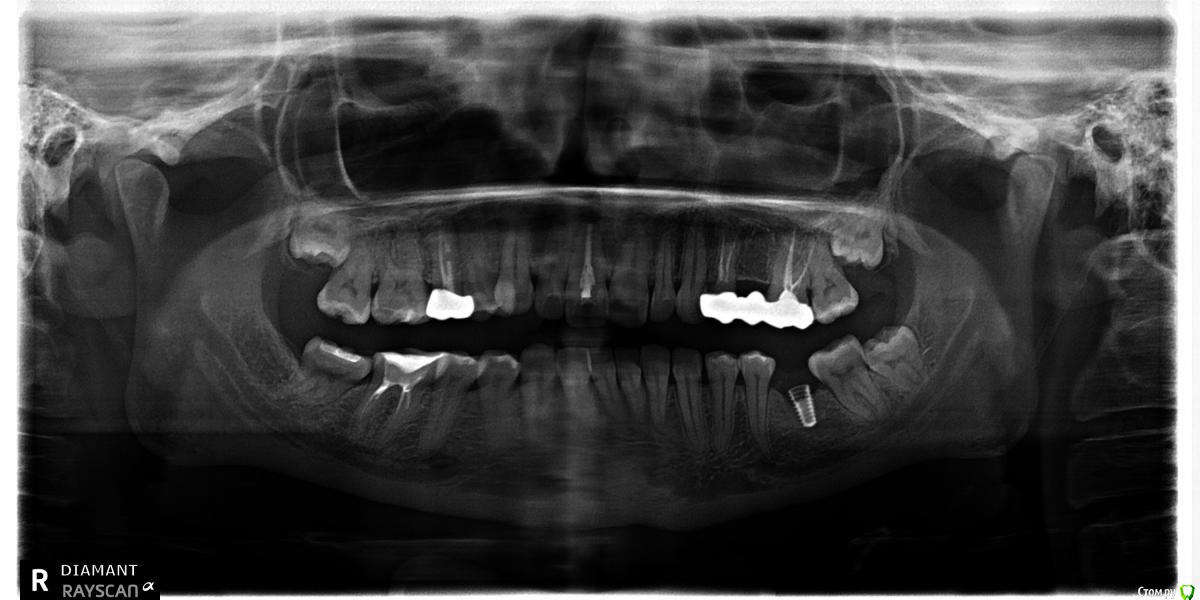

Нина86 Опубликовано 14 августа, 2019 Поделиться Опубликовано 14 августа, 2019 Здравствуйте! Проконсультируйте, пожалуйста, по поломке импланта. 5 лет назад поставила зубной имплант фирмы Megagen (диаметр 4 мм, длина 8,5 мм, Южная Корея, там и ставила).Месяц назад он сломался (сам имплант). На вопрос: "Почему же так произошло?" два стоматолога сказали, что не знают, просто импланты иногда (редко) ломаются. При внимательном рассмотрении панорамных снимков у нас с мужем возник вопрос, а не мог ли имплант сломаться из-за зачатка зуба мудрости, который давил на соседний зуб, а он, в свою очередь, на коронку импланта? Если это могло быть так, то нужно ли удалять зачаток зуба мудрости с той стороны, где имплант, перед установкой нового импланта или это можно сделать после его установки? И последний вопрос: можно ли устанавливать новый имплант в один день с удалением сломанного импланта? Снимки за 2017, март 2019 (до поломки импланта) и за июль 2019 (после поломки импланта) приведены ниже. Огромное спасибо! Ссылка на комментарий

колесников Опубликовано 15 августа, 2019 Поделиться Опубликовано 15 августа, 2019 Почему сломался? Можно только предполагать,но вероятно тут несколько предпосылок к этому было.Во первых ,как видно на снимке,стенка импланта довольно тонкая. Хотя диаметр 4.0 пригоден для установки в области моляров,в данном случае нагрузка оказалось запредельна для стенки такой толщины и для этого сплава . Во вторых ,почему сломался,ведь там внутренний конус? Да на коническом соединении мы получаем минимальную нагрузку на внутреннюю стенку шейки импланта и проблема перелома должна нас не волновать. Но! На корейских системах не оригинальный конус морзе,другой градус,вероятно градус имеет значение.В третьих,так же по снимку можно предположить ,что абатмент платформой «не сел» ,возможно не оригинальный,не правильное распределение нагрузки,как итог микролюфт и переломВ четвёртых,перед фиксацией коронки заметно что имплант более 1/3не в кости. Перелом проходит по костной границе . Вероятно были избыточные боковые нагрузки что привело к микролюфту и перелом произошёл по границе интегрированного с неинтегрированым. Ссылка на комментарий